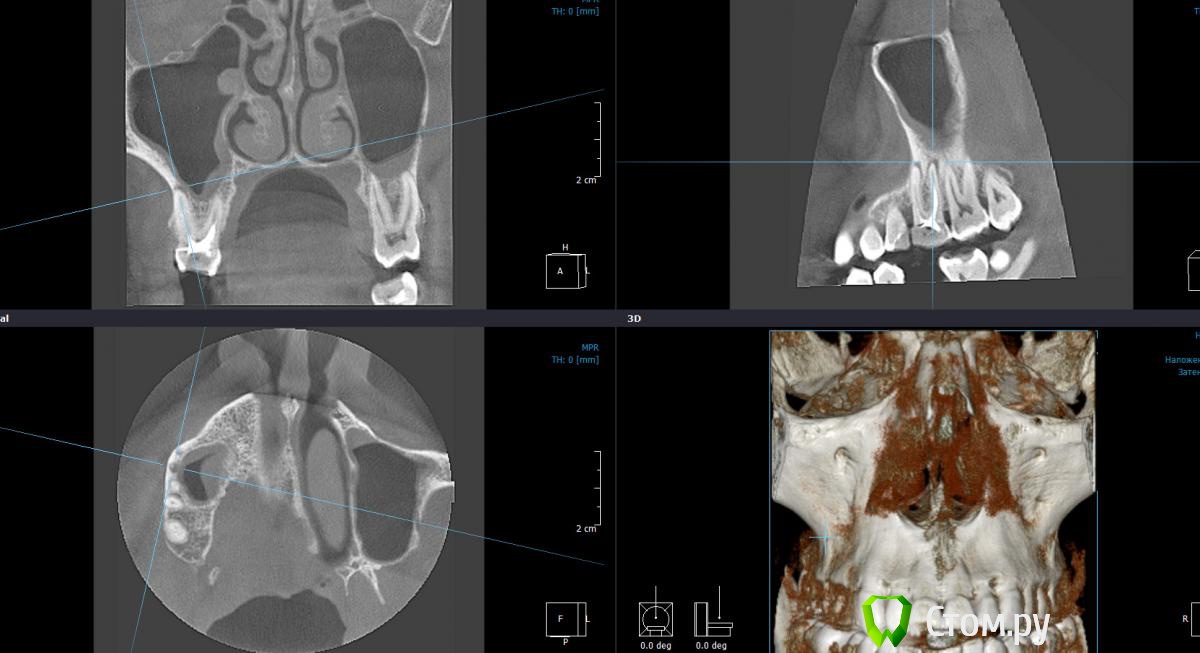

Dtm Опубликовано 1 марта, 2014 Автор Поделиться Опубликовано 1 марта, 2014 Подниму немного свою тему - сделал наконец то КТ, кажется я не ошибался в своих подозрениях на обе верхние 6-ки, что скажут уважаемые доктора? Ссылка на комментарий

Гарриевич Опубликовано 2 марта, 2014 Поделиться Опубликовано 2 марта, 2014 Подниму немного свою тему - сделал наконец то КТ, кажется я не ошибался в своих подозрениях на обе верхние 6-ки, что скажут уважаемые доктора?Нужно перелечивать Ссылка на комментарий

Dtm Опубликовано 3 марта, 2014 Автор Поделиться Опубликовано 3 марта, 2014 Спасибо! На КТ видно что верхушки корней 6 контактируют с ВЧ пазухой - насколько велик риск при перепломбировании (я правильно понял?) вывести пломбировочный материал за верхушку корня в пазухи в данном случае? Ссылка на комментарий

Dtm Опубликовано 3 марта, 2014 Автор Поделиться Опубликовано 3 марта, 2014 Согласен, но для меня как пациента это имеет решающее значение - последствия могут быть неприятные. Может быть безопаснее удалить с имплантацией в перспективе? На левой 6 явно киста у корня? Насколько реально ее пролечить и как, просто сменить пломбу думаю не все, терапия какая то нужна в процессе, я имею ввиду вскрыть, ввести лекарство например? Ссылка на комментарий